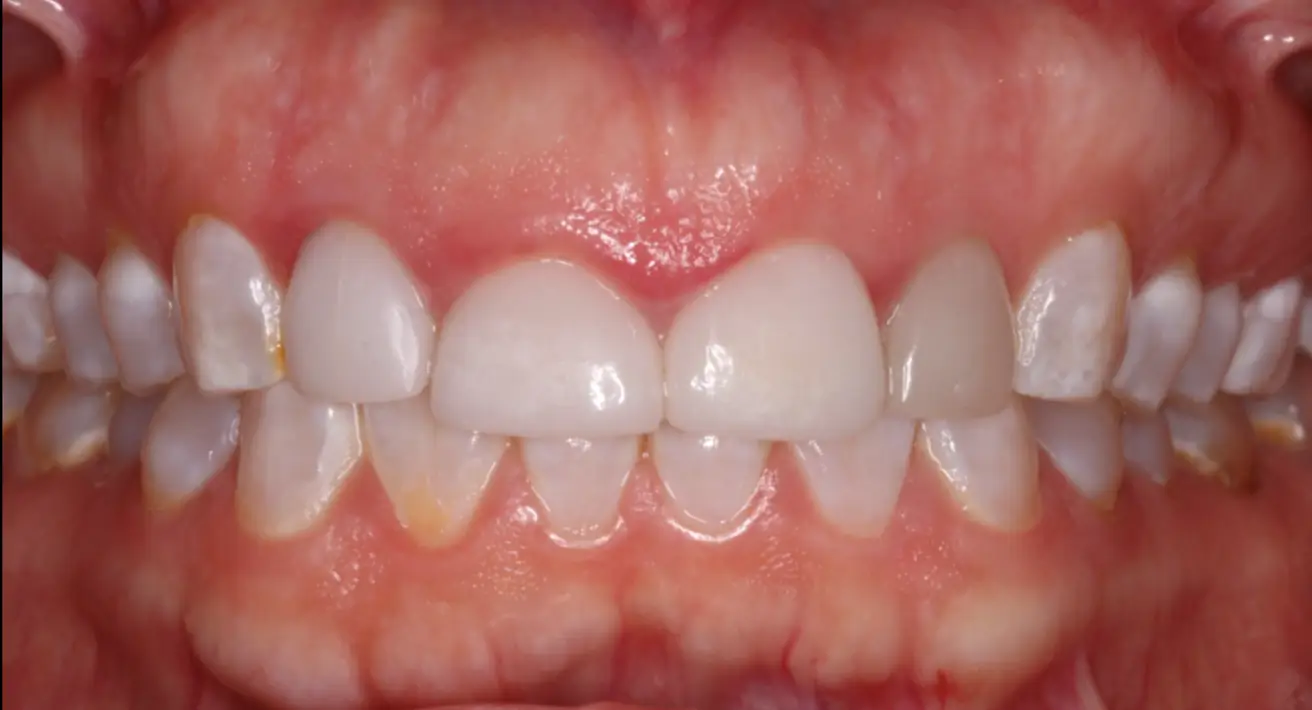

Esthetic Crown Lengthening

before

after